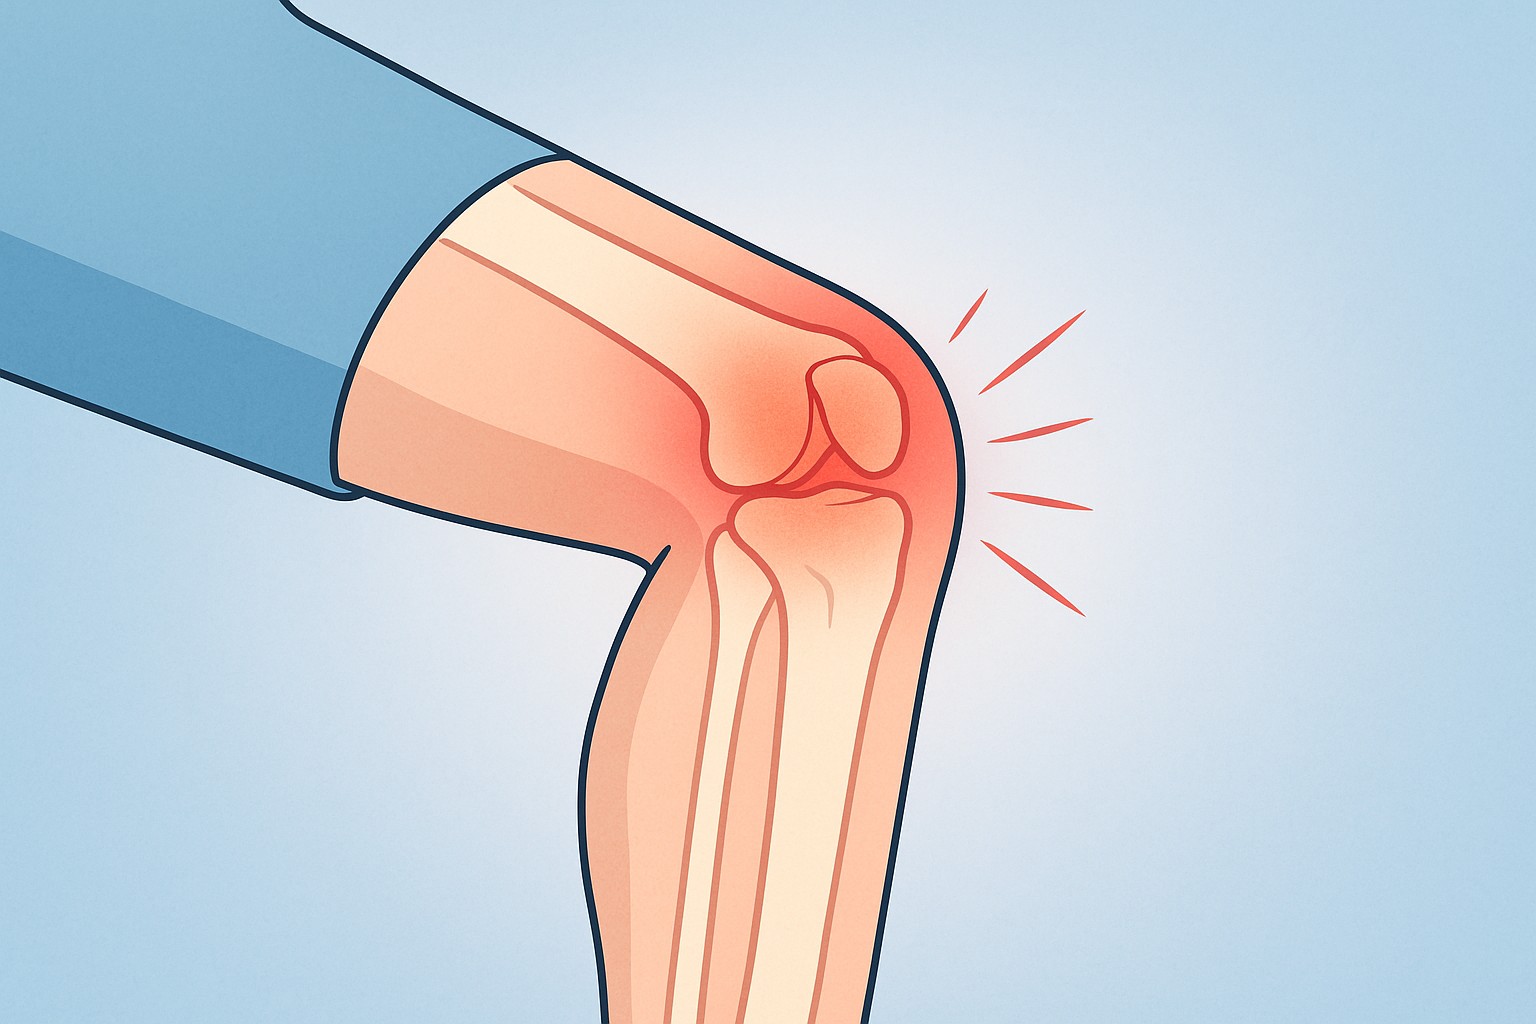

膝という関節の構造と、打撲によるダメージの特徴

膝は骨のすぐ下に軟部組織があるだけで、クッションの層が薄いとされています。そのため、衝撃がダイレクトに骨や関節に伝わりやすいようです(引用元:足立慶友整形外科 https://clinic.adachikeiyu.com/8295、引用元:yoshidaseikei.jp https://www.yoshidaseikei.jp)。

だから「ぶつけただけ」と思っていても、内部の組織に負担がかかる場合があると言われています。

そう思う気持ちもあります。ただ実際には、膝を強打したあとには “関節内出血(血が関節の中にたまる状態)” が起こるケースもあるそうで、これは普通の打撲よりも注意が必要だと言われています(引用元:足立慶友整形外科 https://clinic.adachikeiyu.com/8295、引用元:古東整形外科・リウマチ科 https://koto-orthopaedics.com/occult-fracture)。

と相談されることもありますが、これは膝の内部にある細かい血管が衝撃で傷つくことが理由だと説明される場合があります。血がたまると膝がパンパンに張ったり、曲げ伸ばしがしづらくなったり、痛みが強く感じられることもあるようです。

しかも、この状態のまま無理に曲げたり歩いたりすると、関節の可動域が狭くなったり、炎症が長引くことも指摘されています。

そのため、「曲げると痛い」「膝が熱い」「腫れが強い」といったサインがあるとき、単なる打撲だけとは言えない状況もあると言われています。

「じゃあ全部危ないの?」というと、もちろん軽症のケースもあります。ただ、膝は構造が複雑なので、外からはわかりづらい内部の変化が起きている可能性もあるため、慎重に見たほうが良いと考えられています。

こうした背景から、膝を強くぶつけて曲げると痛いときは、表面だけの問題ではなく、内部で“何かしらの変化が起きている可能性”も想定したほうが良いと言われています。